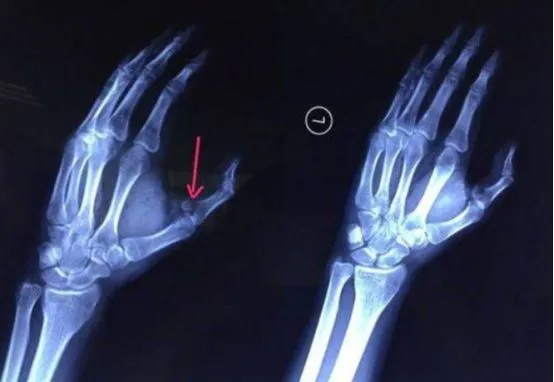

7月29日,20岁的长沙男生小袁从冰箱里拿冷冻的可乐喝,瓶子掉在地上,捡起后开盖瞬间可乐突然爆炸,将他的左手虎口处炸开7厘米长的口子,导致手指骨折。

天啊,怕了怕了~没想到喝个可乐都变得如此危险!